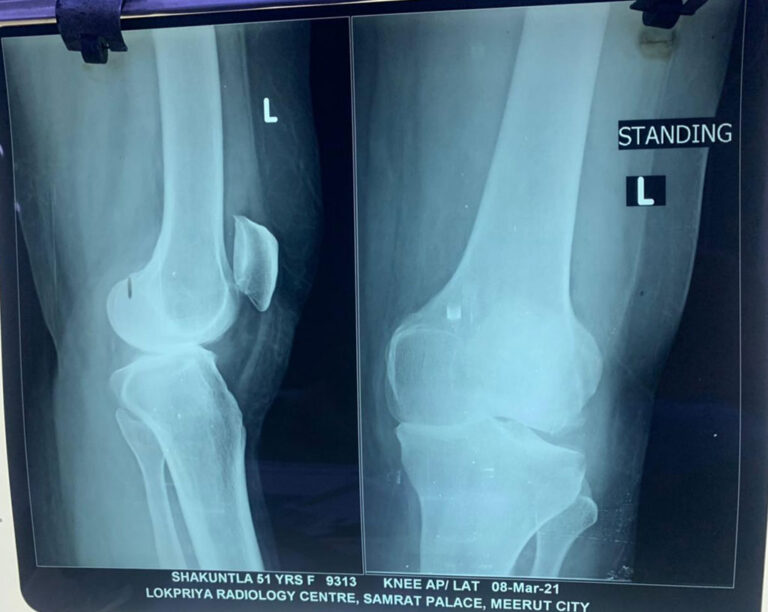

Total Knee Replacement

Name: Shakuntala

Age: 52 Years

Before Surgery